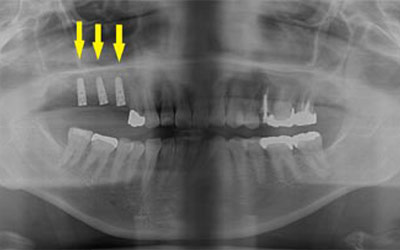

写真は患者様の治療前のレントゲン写真です。右上顎の大臼歯を喪失し、延長ブリッジを装着されていたのですが、支える歯が破折してしまい、抜歯が必要となりました。ここにインプラント治療を行うには、骨が薄くて、困難な状態でした。

CTで見ると、骨が薄いのが良く分かります。黄色の矢印の部分、白く写るのが骨で、矢印のある黒い部分が上顎洞という空洞です。

この空洞部分に、人工骨を入れて、閉鎖しておくと、数か月ほどで骨に置き代わっていき、インプラントを埋入できるだけの骨量になります。サイナスリフトが終了して、数か月経過し、薄かった骨が十分な厚みができたCT画像です。黄色矢印の部分、白く写る骨が増えています。

サイナスリフトを行って、8か月後に、インプラントの埋入手術を行いました。骨が十分にあったので、通常の長さのインプラントが埋入できました。